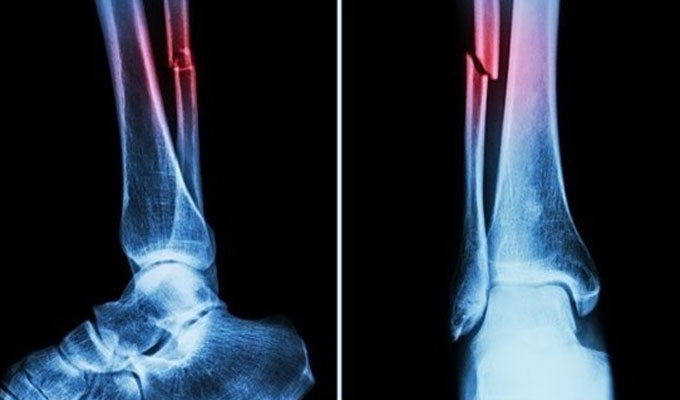

أعلن فريق بحثي في مقاطعة تشيجيانغ شرق الصين عن ابتكار طبي جديد يتمثل في “غراء عظمي” قادر على معالجة الكسور وتركيب الشظايا العظمية خلال ثلاث دقائق فقط، في خطوة وُصفت بأنها اختراق علمي في عالم جراحة العظام، بحسب ما نقل موقع “إن دي تي في” NDTV.

وأكدت الاختبارات المعملية أن Bone-02 نجح في تحقيق نتائج جيدة من حيث السلامة والفعالية. وفي إحدى التجارب، أُجريت العملية في أقل من 180 ثانية (ثلاث دقائق)، بينما كانت طرق العلاج التقليدية تتطلب وقتاً طويلاً لزرع صفائح فولاذية ومسامير.